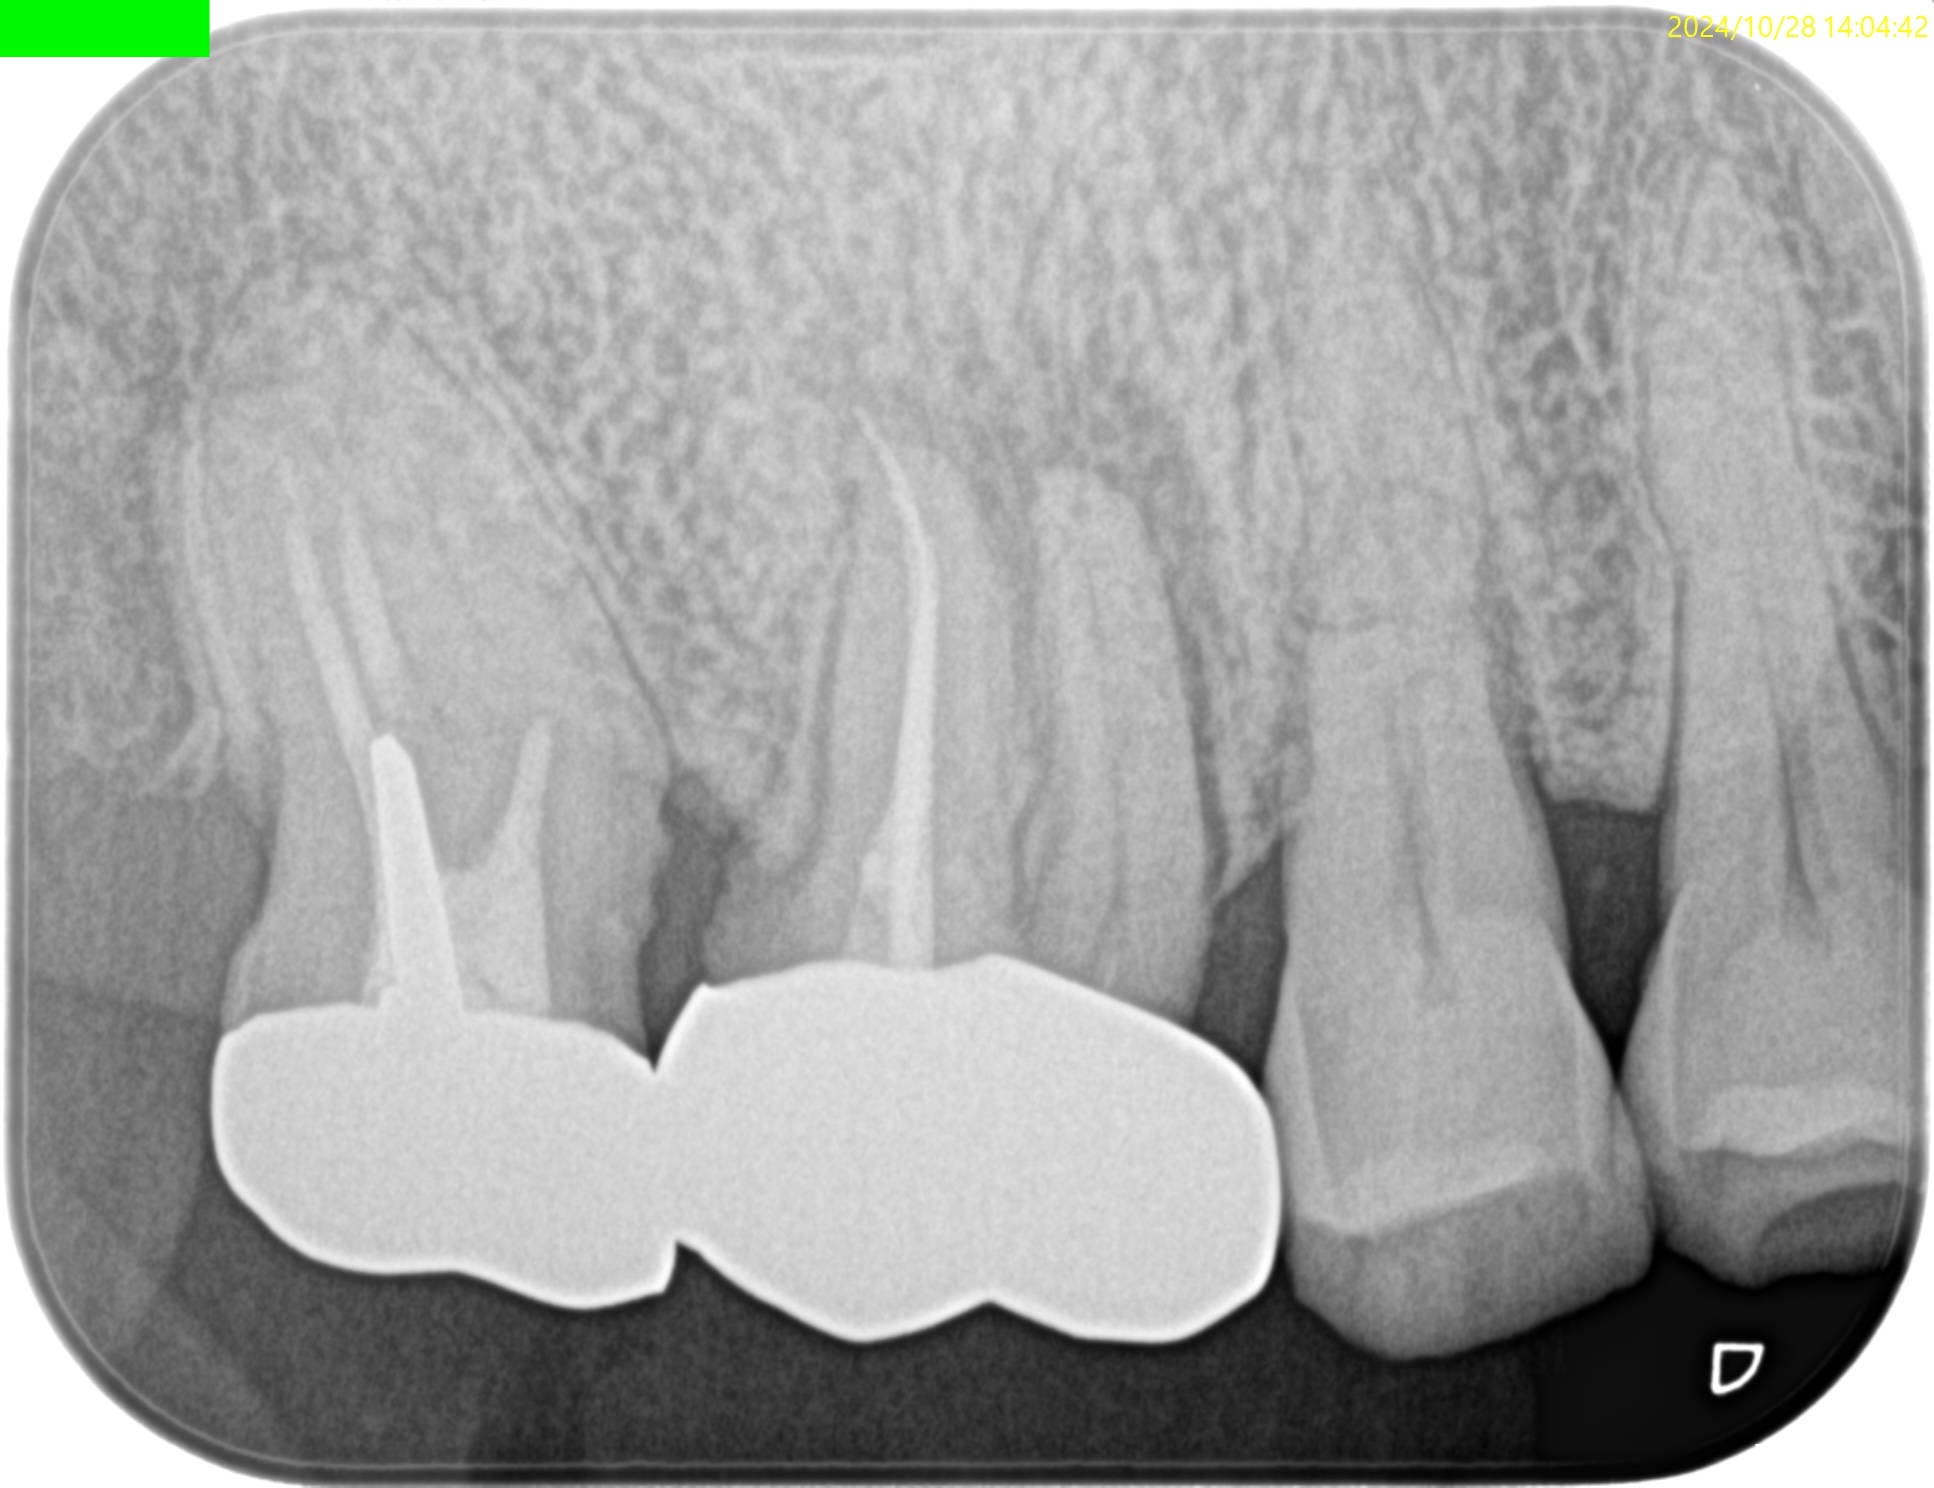

Pre-op PA(2024.11.25)

MBは形成されていない。

ということは通常は根管治療だがSinus tractの存在が治療をApicoectomyへ流れさせている。